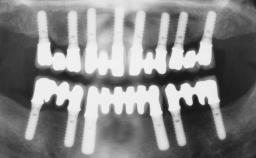

German Gallucci

Boston, United States